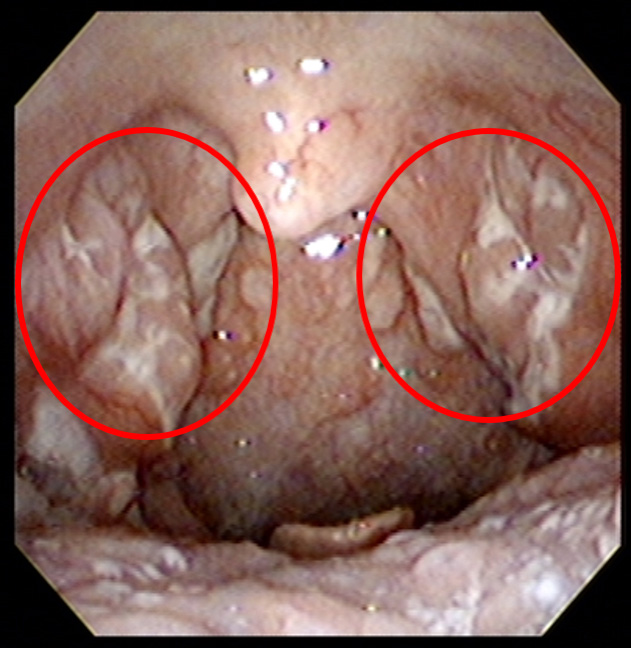

3.眼で見るのどの病気の紹介。